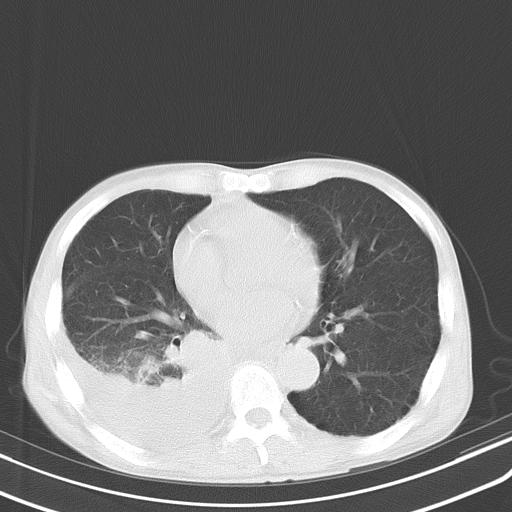

男性 75  咳嗽 一周前发热最高达39

右肺继发型tb并右侧tb性胸腔炎,右侧胸腔大量积液并右下肺膨胀不全,慢支肺气肿、多发肺大泡。建议抽胸水实验室检查并复查排除恶性在占位。

右上肺继发型肺结核,右胸腔中等量积液。

结核的基础上有纵隔淋巴结肿大,右侧有胸水,但右侧纵隔反而窄,说明有肺有不张。

再就是右下肺有块影,和不张混合,还是不能除外肺癌。

补充材料,患者2月份ct片大致正常,双侧胸腔积液,2月份抽胸水未发现ca细胞,现患者发热,痰多,各气管通畅,

1)右肺继发型肺结核。2)左肺胸膜下多发性肺大泡。3)右侧胸腔积液。